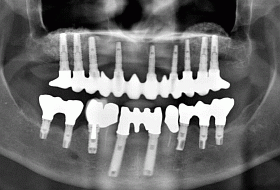

This X-ray shows the final result with the full arch 12 unit dental bridge secured onto 9 Camlog implants (upper jaw) and 4 new dental bridges secured onto 8 Branemark (4 new and 4 previously placed) implants.

Successful sinus lifts and cortical bone transplant, which were required to build up the upper jaw bone, are also visible on this X-ray. Safe placement of implants would not have been possible without those bone augmentation procedures.

This picture shows the final result – 5 dental bridges secured onto 17 implants and 2 existing teeth, which completed full mouth reconstruction and eliminated the need for loose dentures.